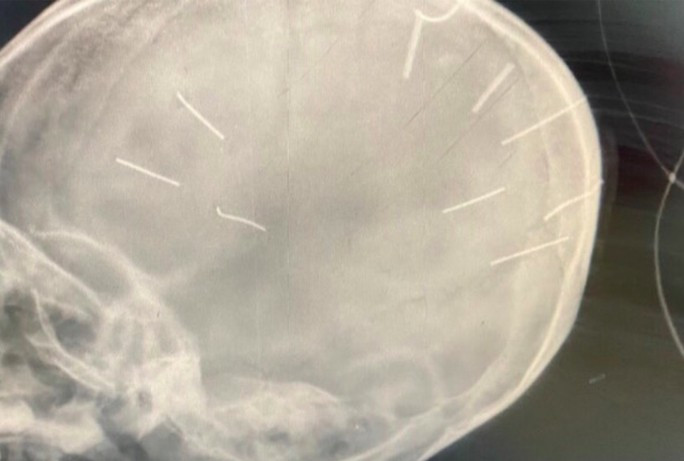

| Hình ảnh đinh trong hộp sọ của bé gái |